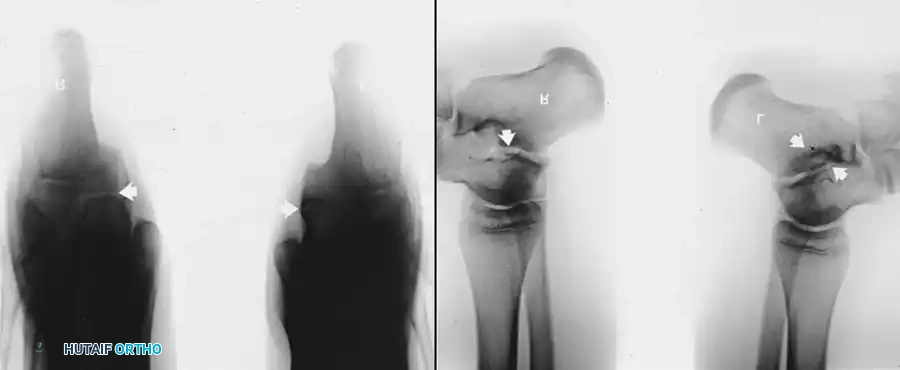

- الأشعة السينية (X-rays):

- للتشخيص المبدئي، يتم التقاط صور بوضعيات خاصة.

- لتشخيص التحام العقب والزورقي، تعتبر الصورة المائلة بزاوية 45 درجة هي الأفضل.

- لتشخيص التحام الكاحل والعقب، يتم استخدام وضعية خاصة تسمى (Harris-Beath view) لتصوير المفصل الأوسط.

- الأشعة المقطعية (CT Scan): تعتبر المعيار الذهبي لتشخيص التحام الكاحل والعقب. توفر صوراً ثلاثية الأبعاد ومقاطع عرضية دقيقة توضح حجم الالتحام، موقعه، وحالة المفاصل المجاورة، مما يساعد الجراح في التخطيط للعملية.

جراحة إزالة التحام العقب والزورقي

في حالة التحام العقب والزورقي، يعتبر الاستئصال الجراحي للجسر العظمي هو الخيار المفضل، خاصة لدى الأطفال والمراهقين الذين لا يعانون من خشونة في المفاصل.

يقوم الجراح بإزالة الجسر العظمي بالكامل لضمان عدم عودته. ولمنع تكوّن العظم مرة أخرى في نفس المكان، يتم وضع نسيج عازل في الفراغ الناتج، مثل جزء من عضلة مجاورة (Extensor digitorum brevis) أو نسيج دهني، أو استخدام الشمع الطبي. أثبتت الدراسات أن هذه الجراحة تنجح بنسبة عالية في تخفيف الألم واستعادة جزء كبير من حركة المفصل.

جراحة إزالة التحام الكاحل والعقب

تُجرى هذه العملية عادة للمرضى الأصغر سناً (10 إلى 15 عاماً) عندما يكون الالتحام في المفصل الأوسط (Middle Facet) صغيراً (أقل من 50% من مساحة المفصل) ولا توجد علامات على خشونة المفاصل.

يتم الدخول جراحياً من الجهة الداخلية للقدم، ويتم استئصال الجسر العظمي بدقة باستخدام أدوات دقيقة حتى يظهر الغضروف السليم للمفصل. كما هو الحال في الالتحام السابق، يتم وضع نسيج دهني أو شمع عظمي لمنع الالتصاق مجدداً.